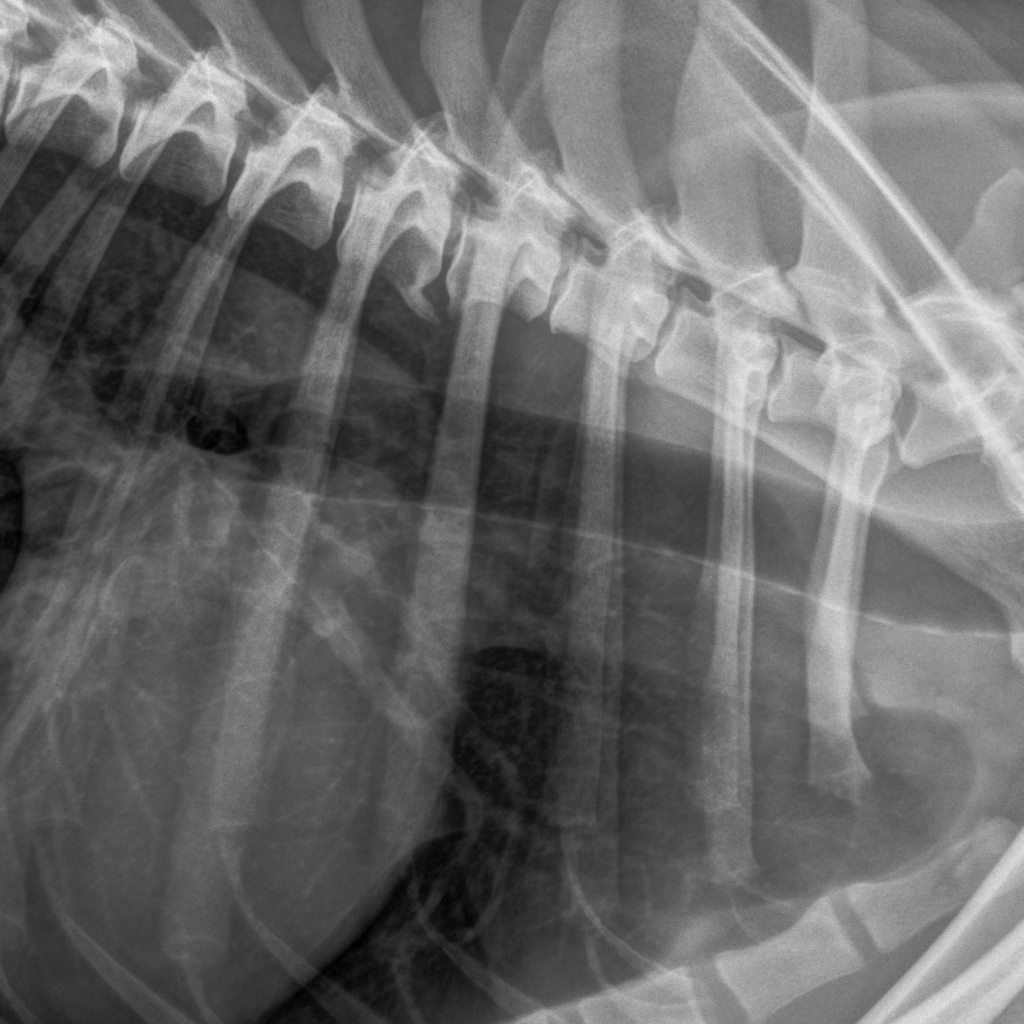

Viralliset selkäkuvat |

Välimuotoinen lanne-ristinikama: LTV0 (normaali) |

Selkäranka, polvet ja olkapäät OK (20.7.12) |

Selkäranka, polvet ja olkapäät OK |

*) Rallin ja Ruskan luustokuvaukset tehtiin 20.7.12 ell Kari Ventelän toimesta.

Roihun luustokuvaukset tehtiin 29.1.13 ell Kirsi Lappalaisen toimesta.

Reinarin luustokuvaukset tehtiin 29.7.13 ell Janne Ojalan toimesta.

Kuvatuissa nivelissä ja selkärangassa ei havaittu muutoksia.